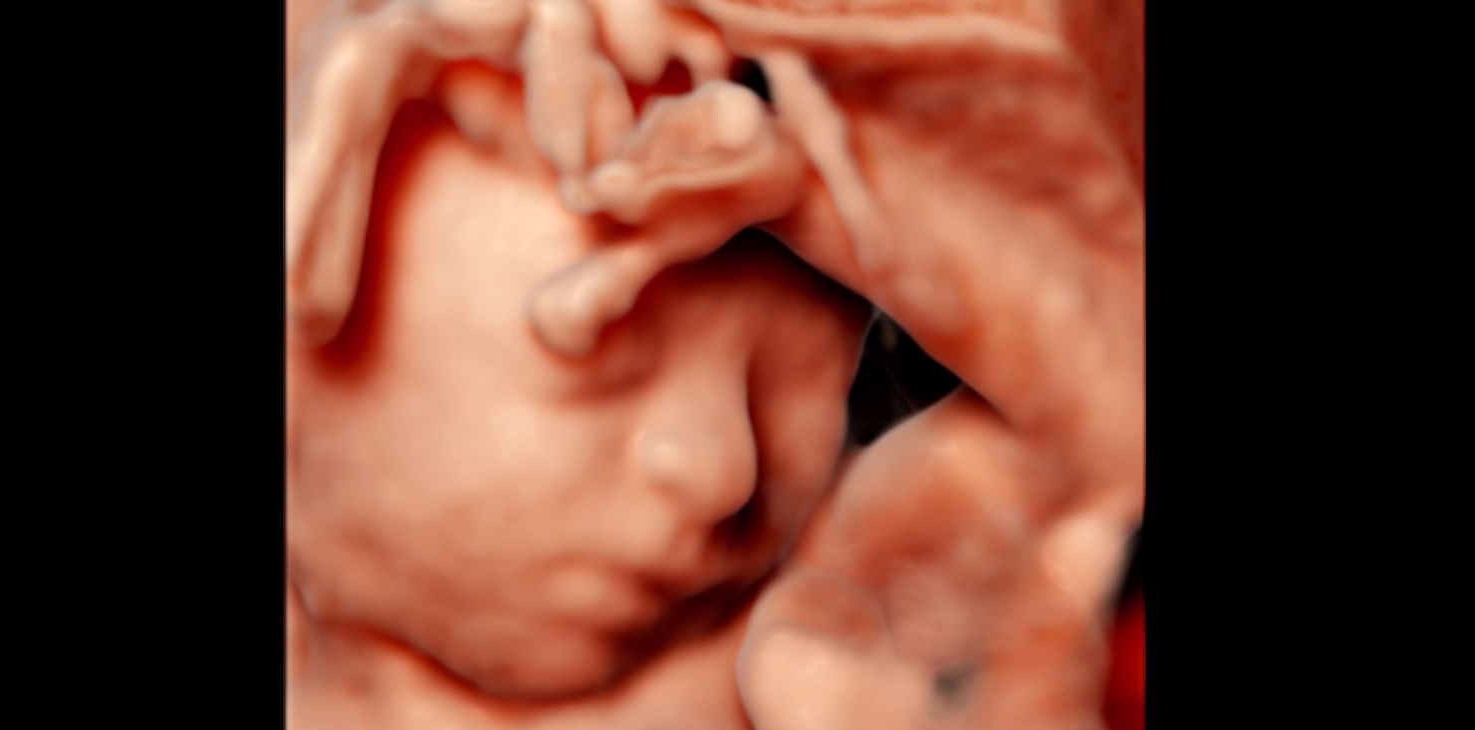

In diesem detaillierten Ultraschall können wir neben der Nackentransparenz bereits die vollständig angelegten Organe Ihres Kindes untersuchen. So erhalten Sie schon früh einen bildlichen Eindruck der ersten Entwicklungsschritte.